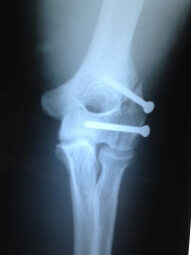

Fractura de Codo - Antes

Fractura de Codo - Después